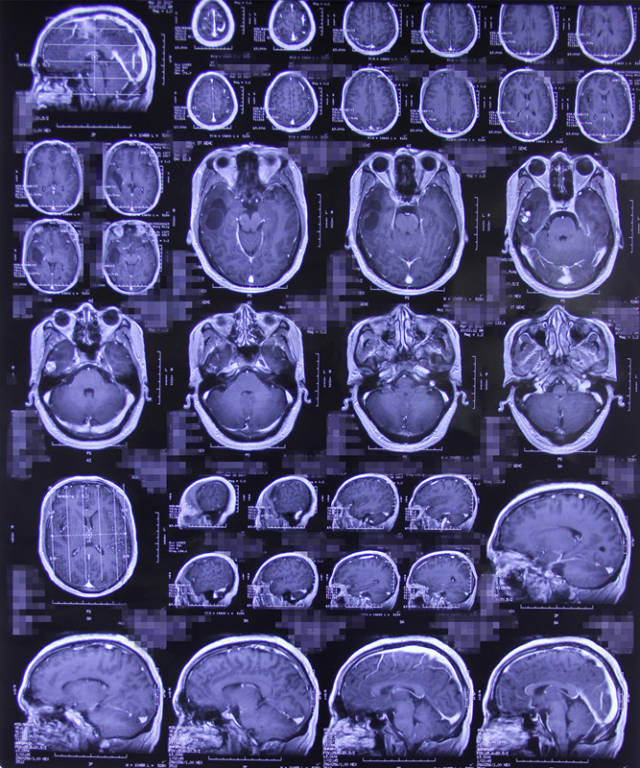

病例:手术切除罕见颅内血管周细胞瘤

2015年江苏省病理年会病例讨论——脑膜血管周细胞瘤